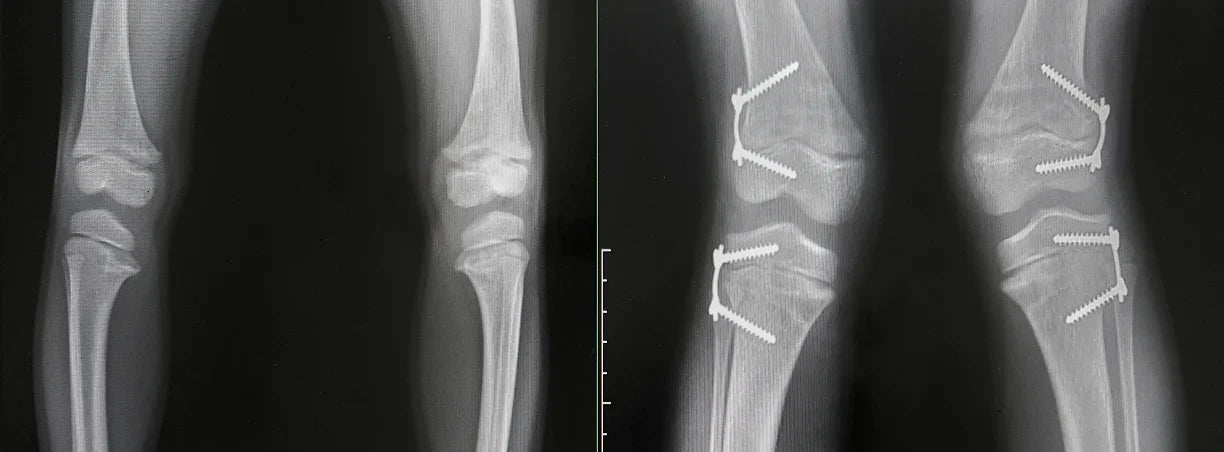

Con ginocchio varo si intende una deformazione anatomica che interessa gli arti inferiori a causa della quale le ginocchia tendono a puntare l’una in direzione opposta all’altra, assumendo una tipica forma arcuata (tanto che uno dei nomi con cui si è soliti riferirsi a questo disturbo è proprio “ginocchia ad arco”).

Contrariamente al ginocchio varo, il ginocchio valgo è una deformità degli arti inferiori che vede le ginocchia tendere verso l’interno, l’una contro l’altra, andando ad assumere una posizione tipicamente a forma di X. Si tratta di un disturbo che si manifesta di frequente in particolare nelle donne a causa della peculiare conformazione del bacino.

In entrambi i casi si è in presenza di un disallineamento tra femore e tibie e per entrambi i disturbi, a seconda della severità, esistono diverse forme di varismo e valgismo: quelle più lievi sono generalmente prive di particolari complicanze, mentre le forme più gravi nel tempo possono avere delle ripercussioni che potrebbero comportare a seconda dei casi problemi nella deambulazione, disturbi ai legamenti del ginocchio, ridotta mobilità articolare e dolori muscolari.